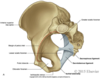

Name the bones of the pelvic girdle

- 1 sacrum

- 5 fused sacral vertebrae

- 2 os coxae

- ilium

- ischium

- pubis

Name the ligaments of the pelvis

- pubic symphysis

- connects 2 pubic bones

- Ant. sacroiliac lig.

- Post. sacroiliac lig.

- sacrotuberous lig.

- sacrospinuos lig.

- obturator membrane Interosseous lig.

Describe the regions of the pelvis

Divided into 2 regions by pelvic brim

- False pelvis

- above pelvic brim pelvic inlet

- continuous with abdominal cavity

- greater pelvis

- True pelvis

- below pelvic brim pelvic outlet

- closed off below by muscular pelvic floor

- lesser pelvis